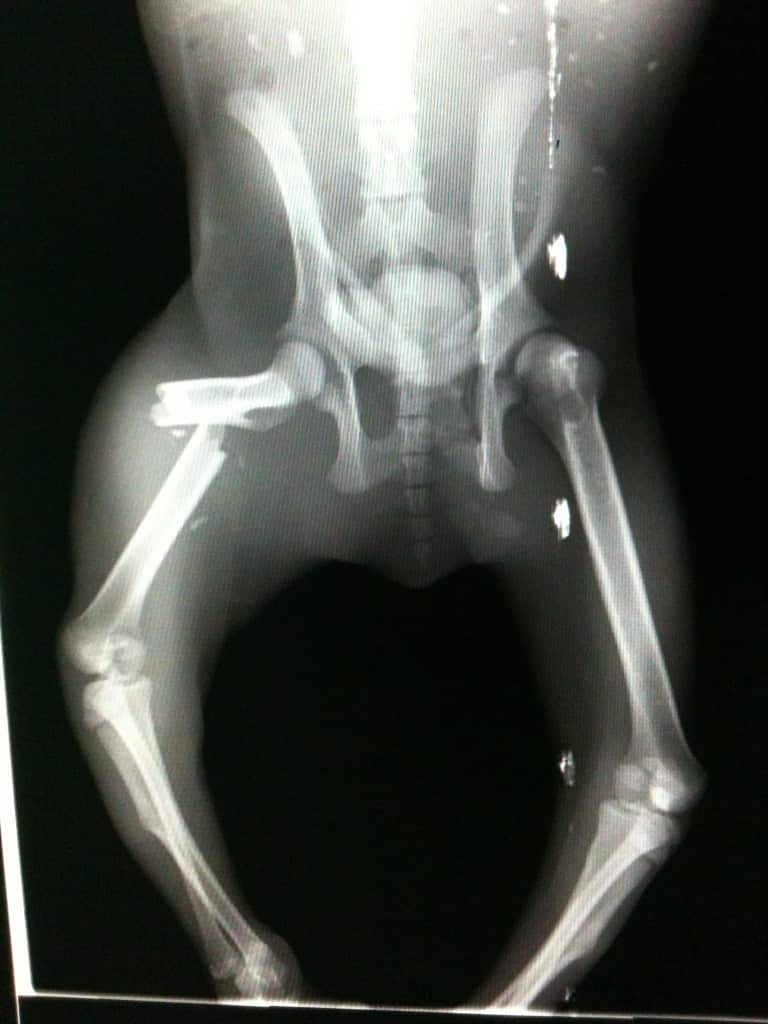

세계자연기금(WWF) 호주지부가 제공한 아래 사진은 2017년 4월 길을 헤매던 코알라가 차에 치이며 골절상을 입은 엑스레이 사진이다.

An X-ray of a koala that suffered a leg fracture after being hit by a vehicle in the Moreton Bay region in April 2017. Source: WWF-Australia